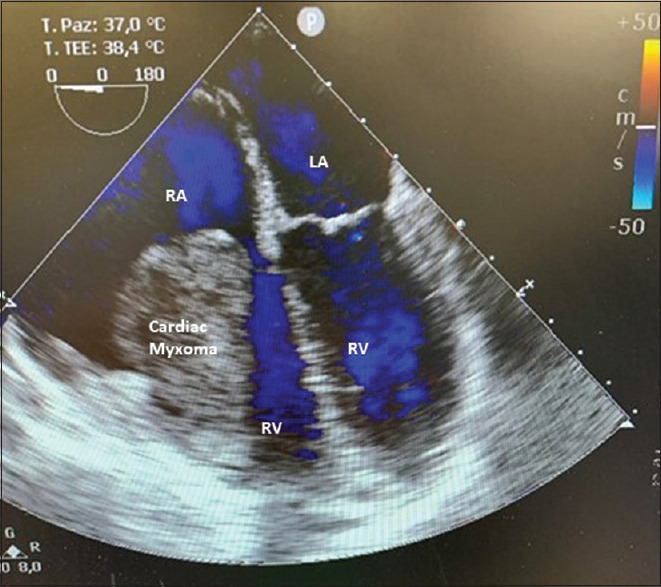

摘要:从右心室延伸出来的心脏肌瘤并不常见,这种罕见的情况可能与多种风险和不良预后有关。我们报告了一例右心室肌瘤患者的病例,该患者近期因动静脉畸形导致出血性中风。术前和术中的处理都极具挑战性,需要医疗团队做出若干艰难的选择,因此,必须采用多学科方法并进行效益风险评估,才能在紧急情况下及时决定手术切除,同时避免延误或不当治疗,在风险极高的情况下取得成功的结果。

Abstract: Cardiac myxomas extending from the right ventricle are uncommon and this rare condition is potentially associated with several risks and poor outcomes. We report the case of a patient with a right ventricular myxoma who had a recent haemorrhagic stroke due to an arteriovenous malformation. The preoperative and intraoperative managements were challenging and required several difficult choices by the medical team and consequently, a multidisciplinary approach and a benefit-risk evaluation were necessary to determinate timely surgical resection in an urgent situation, simultaneously avoiding delayed or improper treatments, achieving a successful outcome in a very high-risk situation.